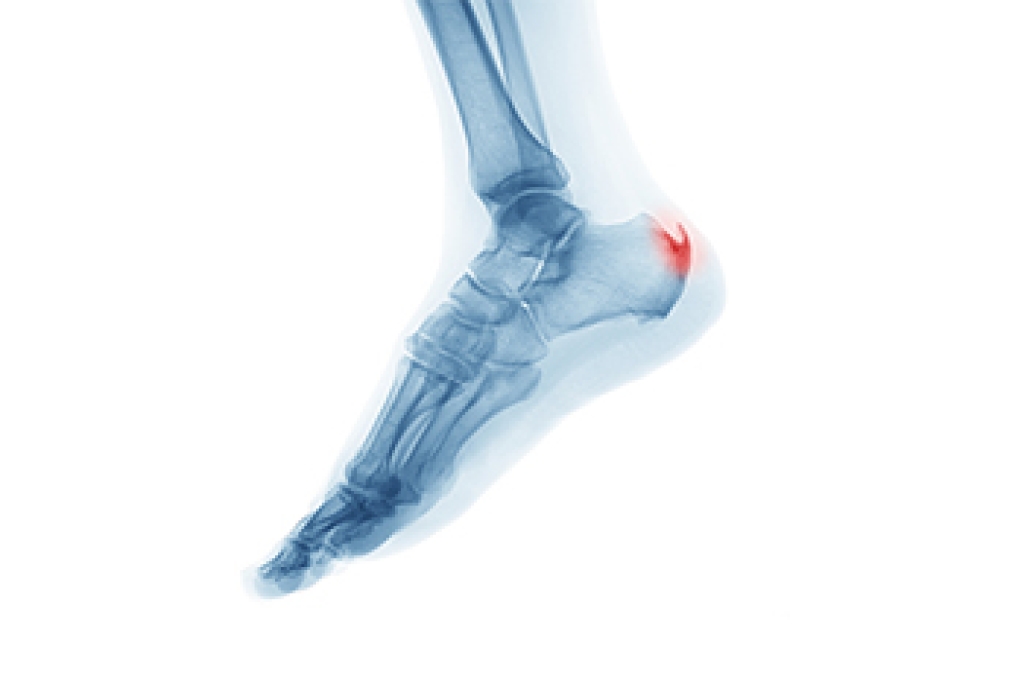

A plantar calcaneal spur, often referred to as a heel spur, is a small bony projection that forms on the underside of the heel bone. It often develops over time as the body responds to repeated strain where the plantar fascia attaches to the heel. This added bone growth may or may not cause pain, but when symptoms are present, they are commonly felt with the first steps after rest or during prolonged standing. The discomfort is often linked more to irritation of the surrounding soft tissue than the spur itself. Evaluation focuses on identifying the source of strain and how the foot functions during movement. Treatment may include wearing supportive footwear, cushioning, stretching, and custom orthotics to reduce pressure on the heel. Addressing contributing factors early can help limit ongoing irritation and improve comfort. If heel pain is affecting your daily routine, it is suggested that you see a podiatrist for a proper diagnosis and appropriate treatment.

Heel spurs are formed by calcium deposits on the back of the foot where the heel is. This can also be caused by small fragments of bone breaking off one section of the foot, attaching onto the back of the foot. Heel spurs can also be bone growth on the back of the foot and may grow in the direction of the arch of the foot.